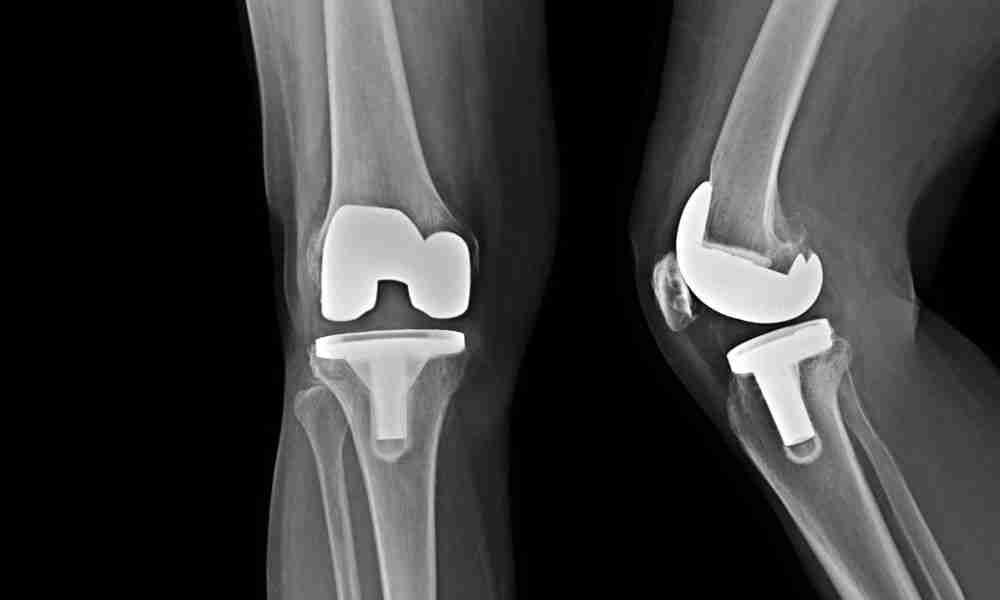

Medicare provides coverage for hospital stays and surgeries through different parts of the program. Part A covers inpatient hospital care, which includes expenses for the room, meals, and nursing services. Meanwhile, Part B covers medically necessary surgeries, including the surgeon’s fees and anesthesia.

Medicare covers surgeries deemed medically necessary, such as hip, knee, and shoulder replacements. Check with your provider for specific details.